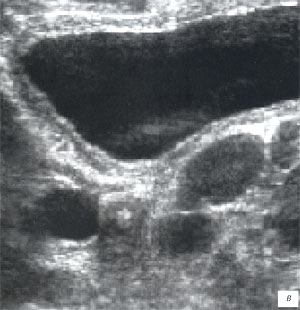

Мезентериальные лимфатические узлы: УЗИ и диагностика

Раздел: Лаборатория идей